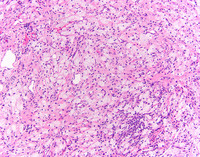

High power H&E

At higher power, foamy histocytes with bland nuclear morphology occurring singly and in aggregates are noted. These cells are characterized by vacuolated cytoplasm,  often in a fibrotic background with admixed chronic inflammation.